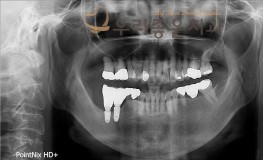

우리좋은치과 치아 상실로 인한 임플란트 보철 치료 (최** 2019.04.09~11..

No.348

임플란트

2019-11-25

1579